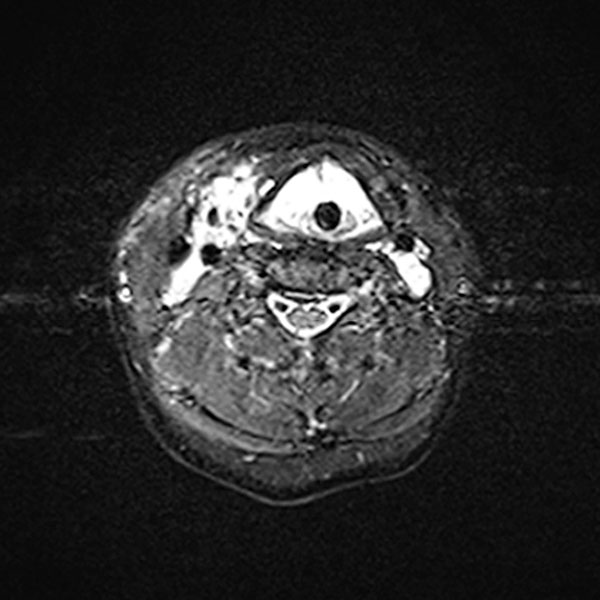

In der transversalen T2-gewichteten, fettunterdrückten MRT des Halses sind ebenfalls ausgedehnte, stark hyperintense (weiße) Anteile der venösen Malformation am Larynx und Hals sichtbar. Diese engen die oberen Atemwege massiv ein. Zentral erkennbar der liegende Endotrachealtubus.